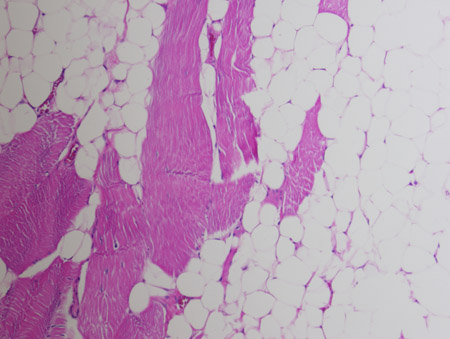

[Figure caption and citation for the preceding image starts]: Intramuscular lipoma. Mature adipose tissue insinuating between skeletal muscle bundles. Haematoxylin and eosin, 200x magnificationFrom the collection of Dr Kimberly Moore Dalal and Dr Steven D. DeMartini; used with permission [Citation ends].